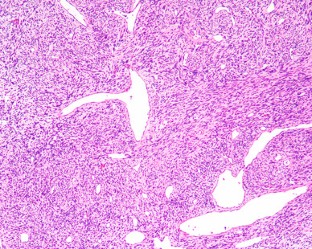

Solitary fibrous tumors (SFTs) are well recognized in the head and neck region, but rarely arise in the sinonasal tract (SNT). Six primary SNT SFTs were identified in the files of Southern California Permanente Medical Group between 2006 and 2017. The patients included five males and one female ranging in age from 33 to 72 years (mean 52 years), most of whom presented clinically with nasal obstruction. Three tumors involved the nasal cavity alone, one involved the paranasal sinuses, and two involved both the nasal cavity and paranasal sinuses. Histologically, the tumors were characterized by a variably cellular proliferation of cytologically bland spindle cells within a collagenous stroma with prominent interspersed branching vessels. Mitotic activity was low (range 0–2 per 10 high power fields) and there was no evidence of pleomorphism or tumor necrosis. Surface ulceration was noted. By immunohistochemistry, the lesional cells were positive for CD34, STAT6 and bcl-2. Clinical follow up information was available for all patients (range 32–102 months; mean 72 months). There were no recurrences or metastases and all were alive with no evidence of disease at last follow-up. SFTs rarely affect the SNT, but should be considered in the differential diagnosis of SNT mesenchymal lesions. Immunohistochemical expression of STAT6 can aid in diagnosis and separation of SFT from other spindle cell lesions occurring at this anatomic site. In combination with cases reported in the literature, primary SNT SFT behave in an indolent manner with conservative treatment.

Fig. 1